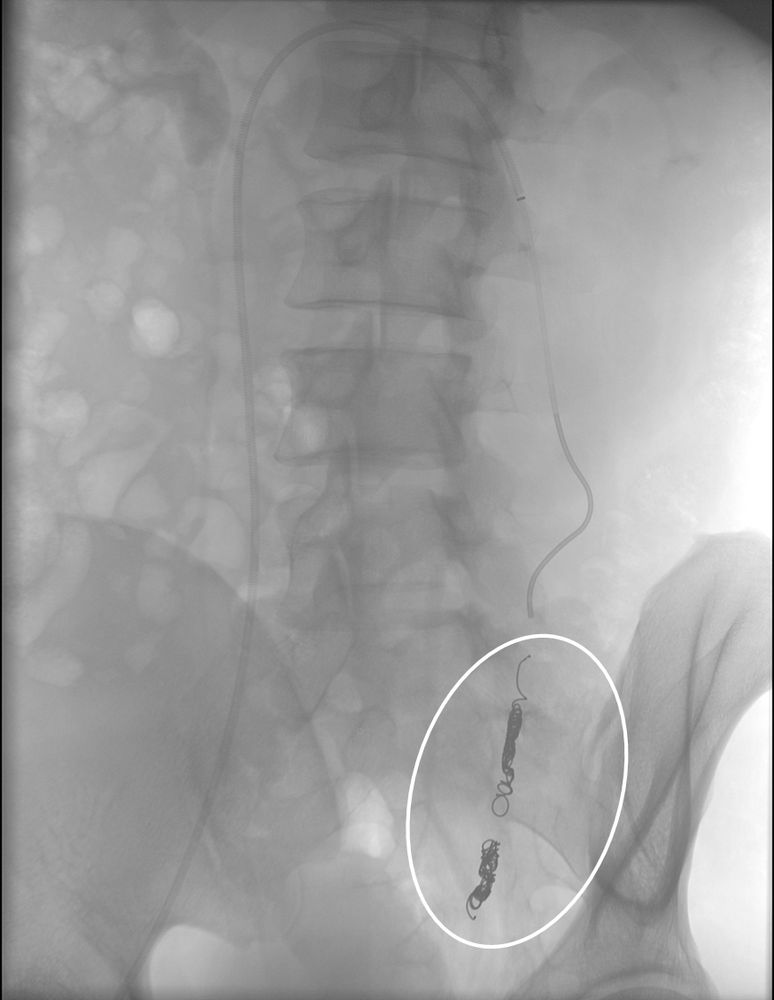

Συνοπτικά υπό την καθοδήγηση του αγγειογράφου, αναγνωρίζεταιτο παθολογικό αγγείο-αγγεία και με ειδικούς καθετήρες και μικροκαθετήρες, διοχετεύονται εμβολικά υλικάόπως μικροσφαιρίδια ή coils, ώστε να αποφραχθεί ή να μειωθεί η παθολογική αγγείωση.